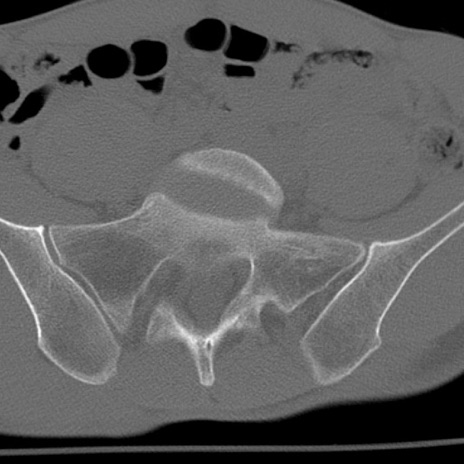

症例3 腰椎CT(横断像)

腰椎CT